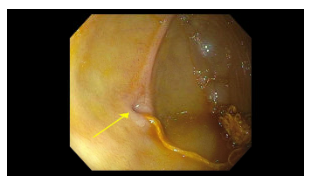

Endoscopy findings: There was a narrowed opening (different orientation of same narrowing in both pictures) with a string-like material.

Surgical findings: A duodenal web with a piece of lint was identified. The patient had a laparoscopic wedge excision with a transverse closure of the duodenotomy. The lint may have occluded the tiny opening of the web that he had been living with since he was born.

My take: This is the first time I have seen the endoscopic appearance of a duodenal web.